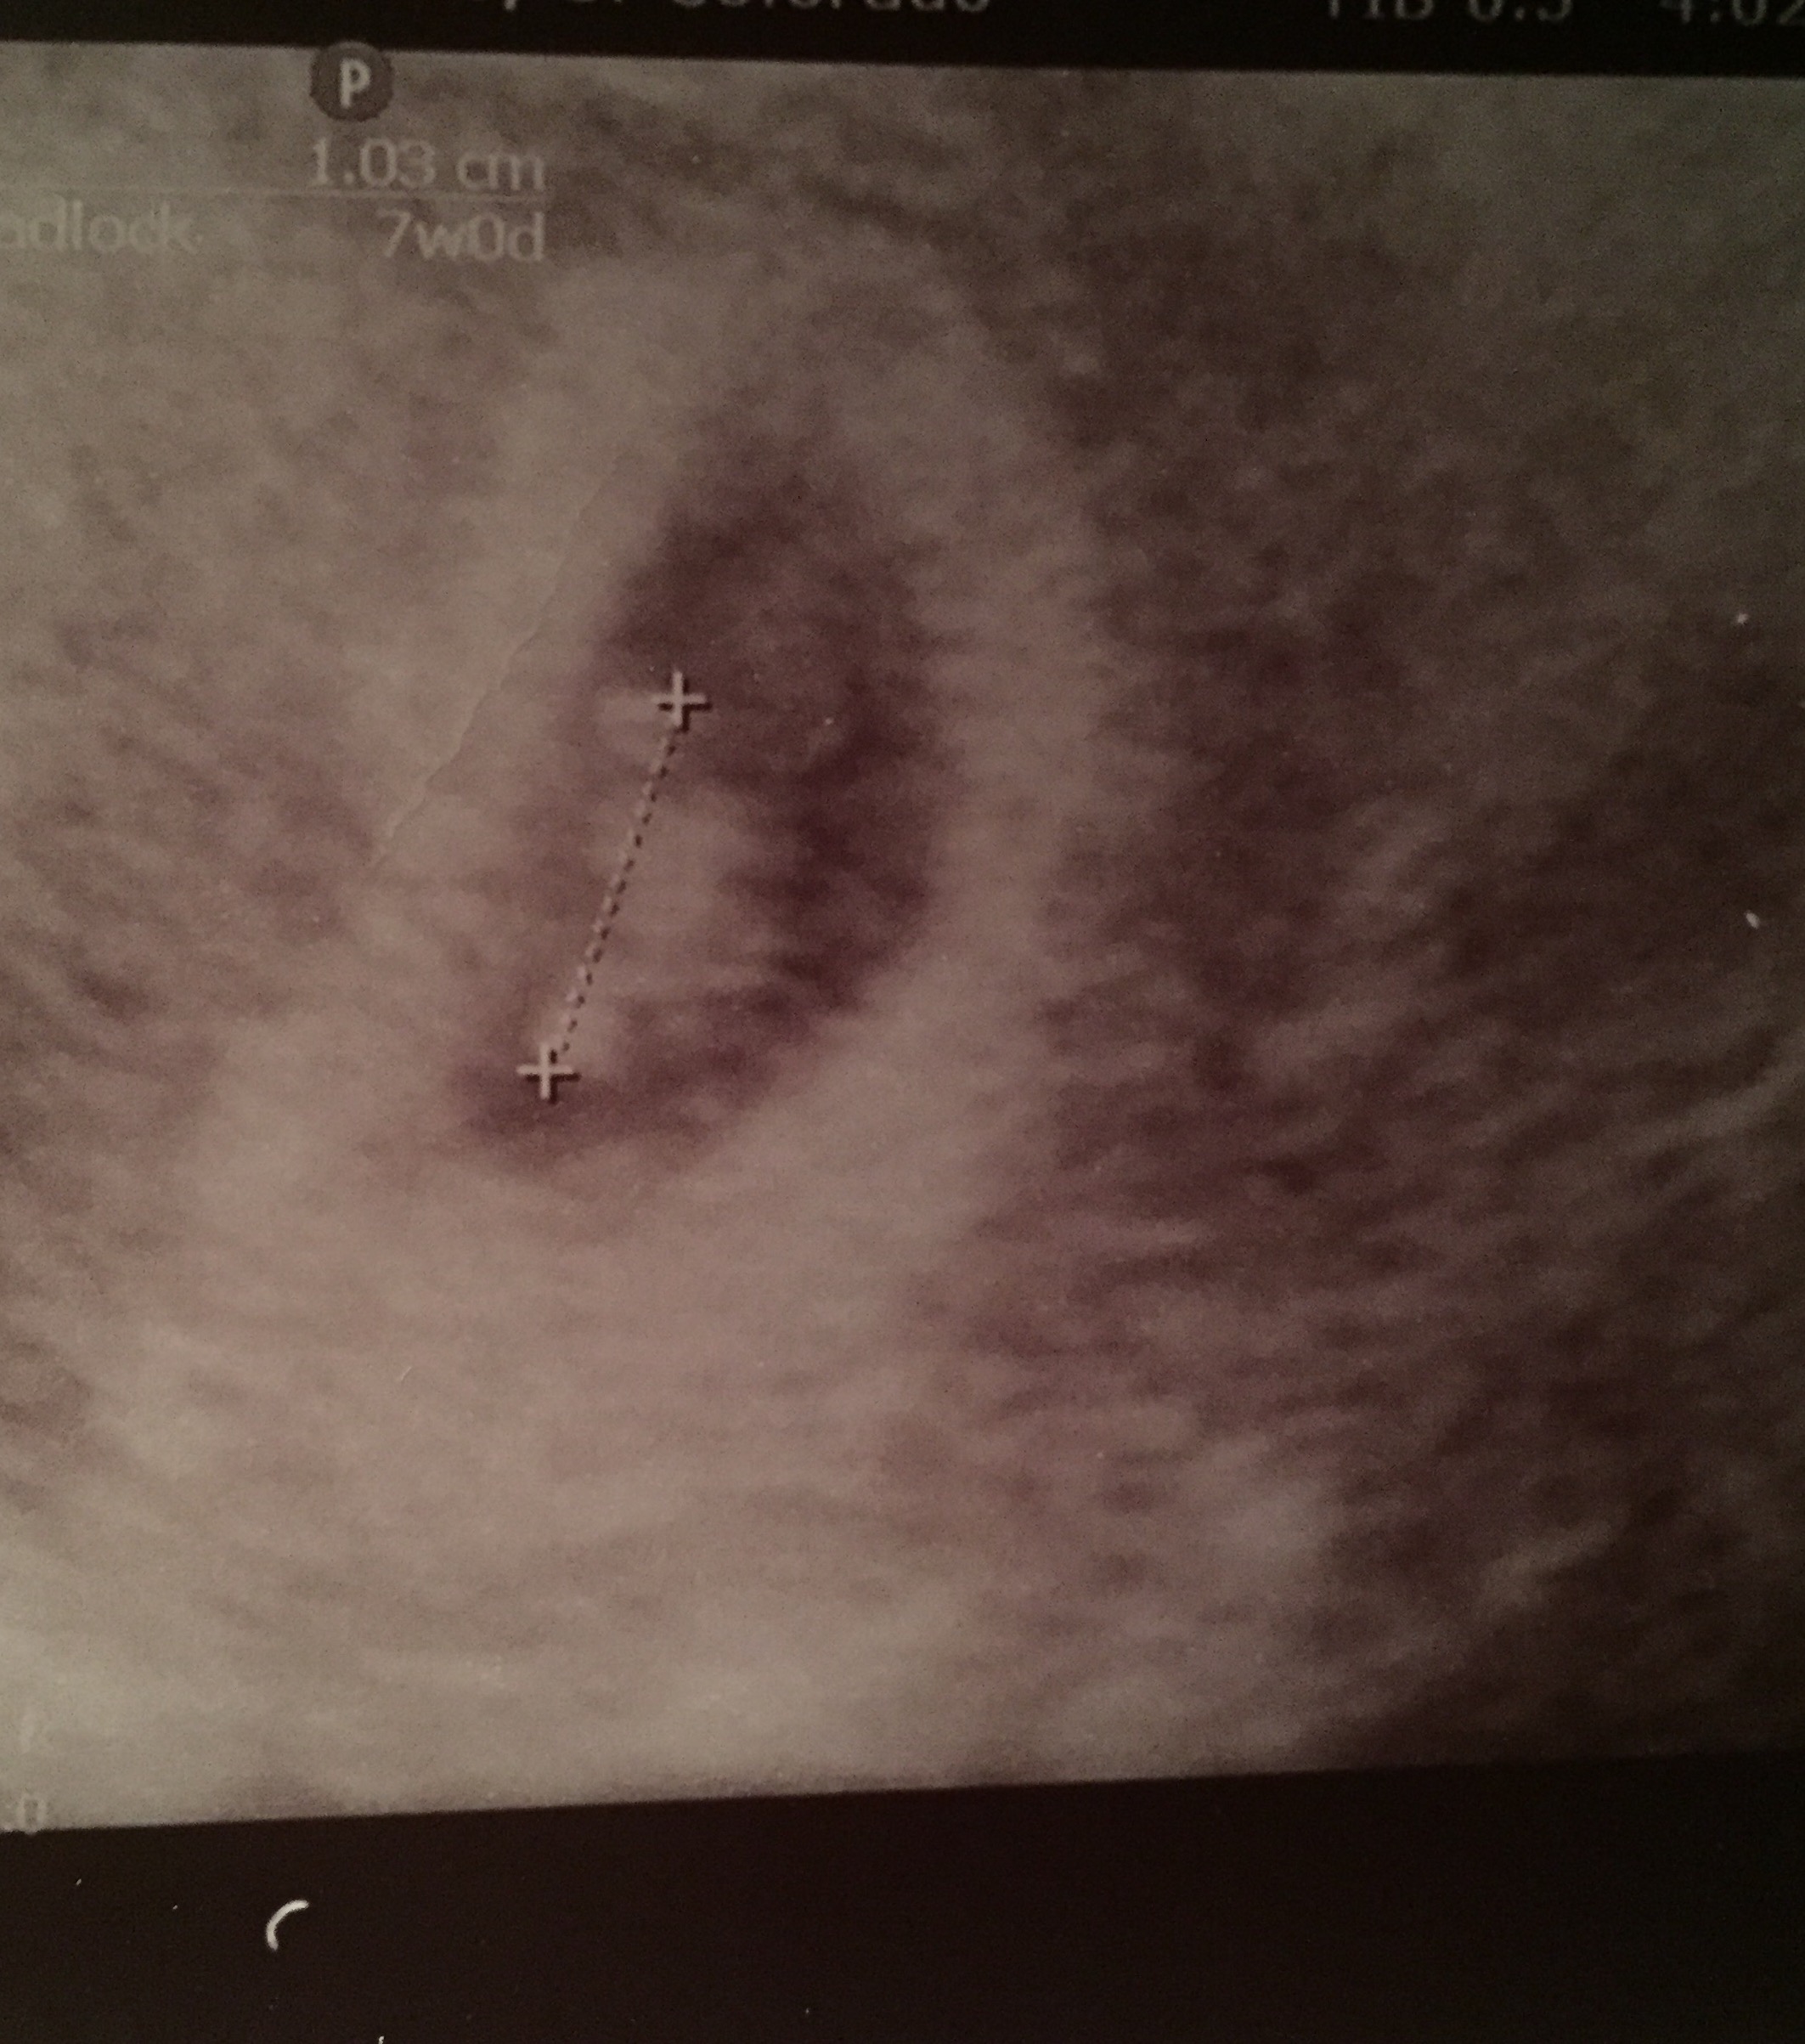

We had our first ultrasound today. Measured at 6 was 3 days which is pretty much right on track. He/she is tiny but we already heard the heartbeat at 124 bpm. We have one every week from now until the end of the first trimester so can't wait to watch the growth.

Not a great photo, but we saw the little flicker of the heartbeat!